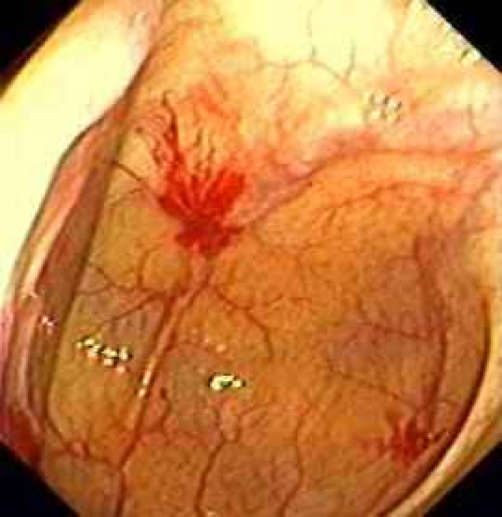

Acquired malformation of submucosal and mucosal blood vessels: Most common location? Why?

Angiodysplasia: cecum largest diameter

tortuous dilation of vessels–> hematochezia

accounts for 20% of major episodes of lower intestinal bleeding

Angiodysplasia: BRIGHT RED BLOOD